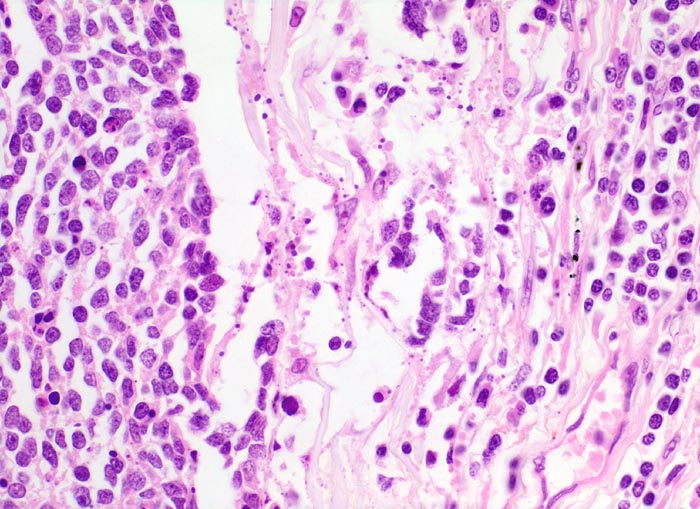

Die monomorphen rundlichen, fusiformen oder polygonalen Tumorzellen haben sehr wenig Zytoplasma, die Kerne sind hyperchromatisch und Nukleolen sind kaum zu erkennen. Die Tumorzellen bilden lockere Verbände, bandförmige Anordnungen oder Pseudorosetten um Gefässe. Oftmals zeigen die Tumoren in der Biopsie charakteristische Quetschartefakte. Ein histologisches Grading wird im Gegensatz zu den nicht kleinzelligen Karzinomen nicht vorgenommen. An kleinen Biopsien kann die morphologische Unterscheidung eines kleinzelligen Karzinoms von einem Lymphom bzw. von normalem lymphatischem Gewebe schwierig sein (> 1101). Diese Unterscheidung gelingt aber meist problemlos mit Hilfe einer immunhistochemischen Zusatzuntersuchung (> 1100).

• Tumorzellen mit sehr schmalem Zytoplasmasaum ("nacktkernig").

• Eckige, ovale oder rundliche Kerne mit uniform feinkörnigem Pfeffer und Salz Chromatin.

• Tumorzellkerne etwa dreimal so gross wie Lymphozytenkerne.

• Nukleolen sind nicht erkennbar oder sehr klein.

• Herdförmig Quetschartefakte (langgezogene Kernschlieren).

• Sehr zahlreiche Apoptosen und kleinherdige Tumornekrosen.